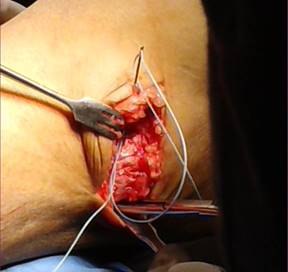

El procedimiento se llevó a cabo en la sala quirúrgica. Se colocó isquemia en el miembro inferior que se intervino y control con manguito neumático. Se realizó un abordaje lateral oblicuo en tobillo a nivel del maléolo externo de aproximadamente 5 cm. Se disecó por planos, teniendo especial cuidado con el nervio peroneo superficial. Se identificó la articulación tibioastragalina, astrágalo y peroné distal. Se localizó el ligamento peroneoastragalino anterior y peroneocalcáneo. Se observó su integridad y se realizaron maniobras transquirúrgicas de estrés en varo y cajón anterior. Se valoró su competencia. En caso de estar lesionados, se acortaron y se unieron extremos, o bien, se insertaron en sus orígenes, dependiendo el caso. Se procedió a la colocación del ancla. Se fijó la misma a la región anterior del astrágalo o bien al calcáneo en caso de estar lesionado, también el ligamento peroneocalcáneo, con otra ancla. Se realizó un túnel en el extremo distal del peroné de anterior a posterior con una broca 2.5. Se colocó la sutura a través de dicho túnel y se fijó mediante nudos simples dando tensión a manera de reforzar la reparación. De nuevo se comprueba la competencia ligamentaria. Por último, se anteriorizó el retináculo extensor (Figuras 1 a 4).